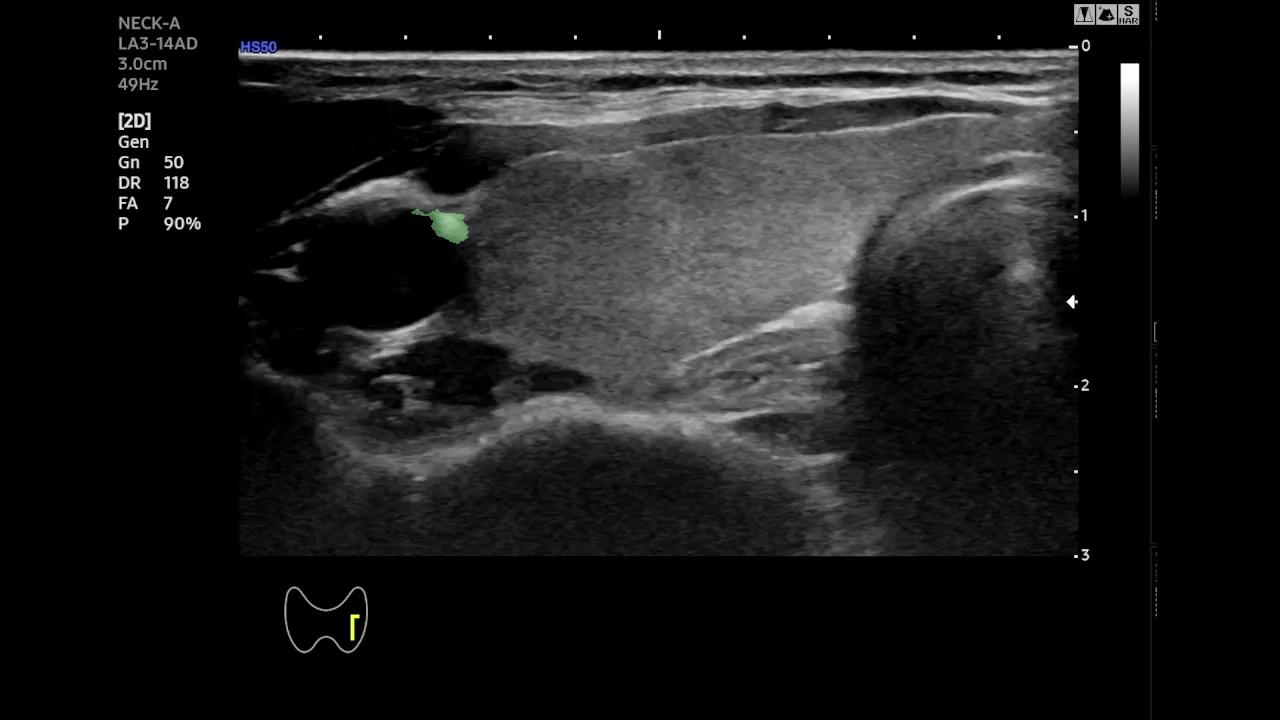

Qualitative Analysis of Temporal Stability- To better highlight the temporal behavior of SAM-2 and EMA-SAM, we visualize predictions at representative frames sampled from a complete RFA sequence. Figure 2 shows a three-row comparison: the first row displays the original ultrasound frames at selected timestamps (with ellipses indicating omitted intermediate frames), the second row shows SAM-2 predictions, and the third row presents EMA-SAM results. As the sequence progresses, SAM-2 occasionally loses the PTMC region when it becomes indistinct or is occluded by RFA bubbles, sometimes mis-segmenting nearby tissue. In contrast, EMA-SAM maintains a coherent segmentation trajectory throughout the sequence. Its confidence-weighted exponential-moving-average pointer preserves a robust latent prototype of the lesion, allowing rapid re-identification and boundary recovery once the PTMC reappears.